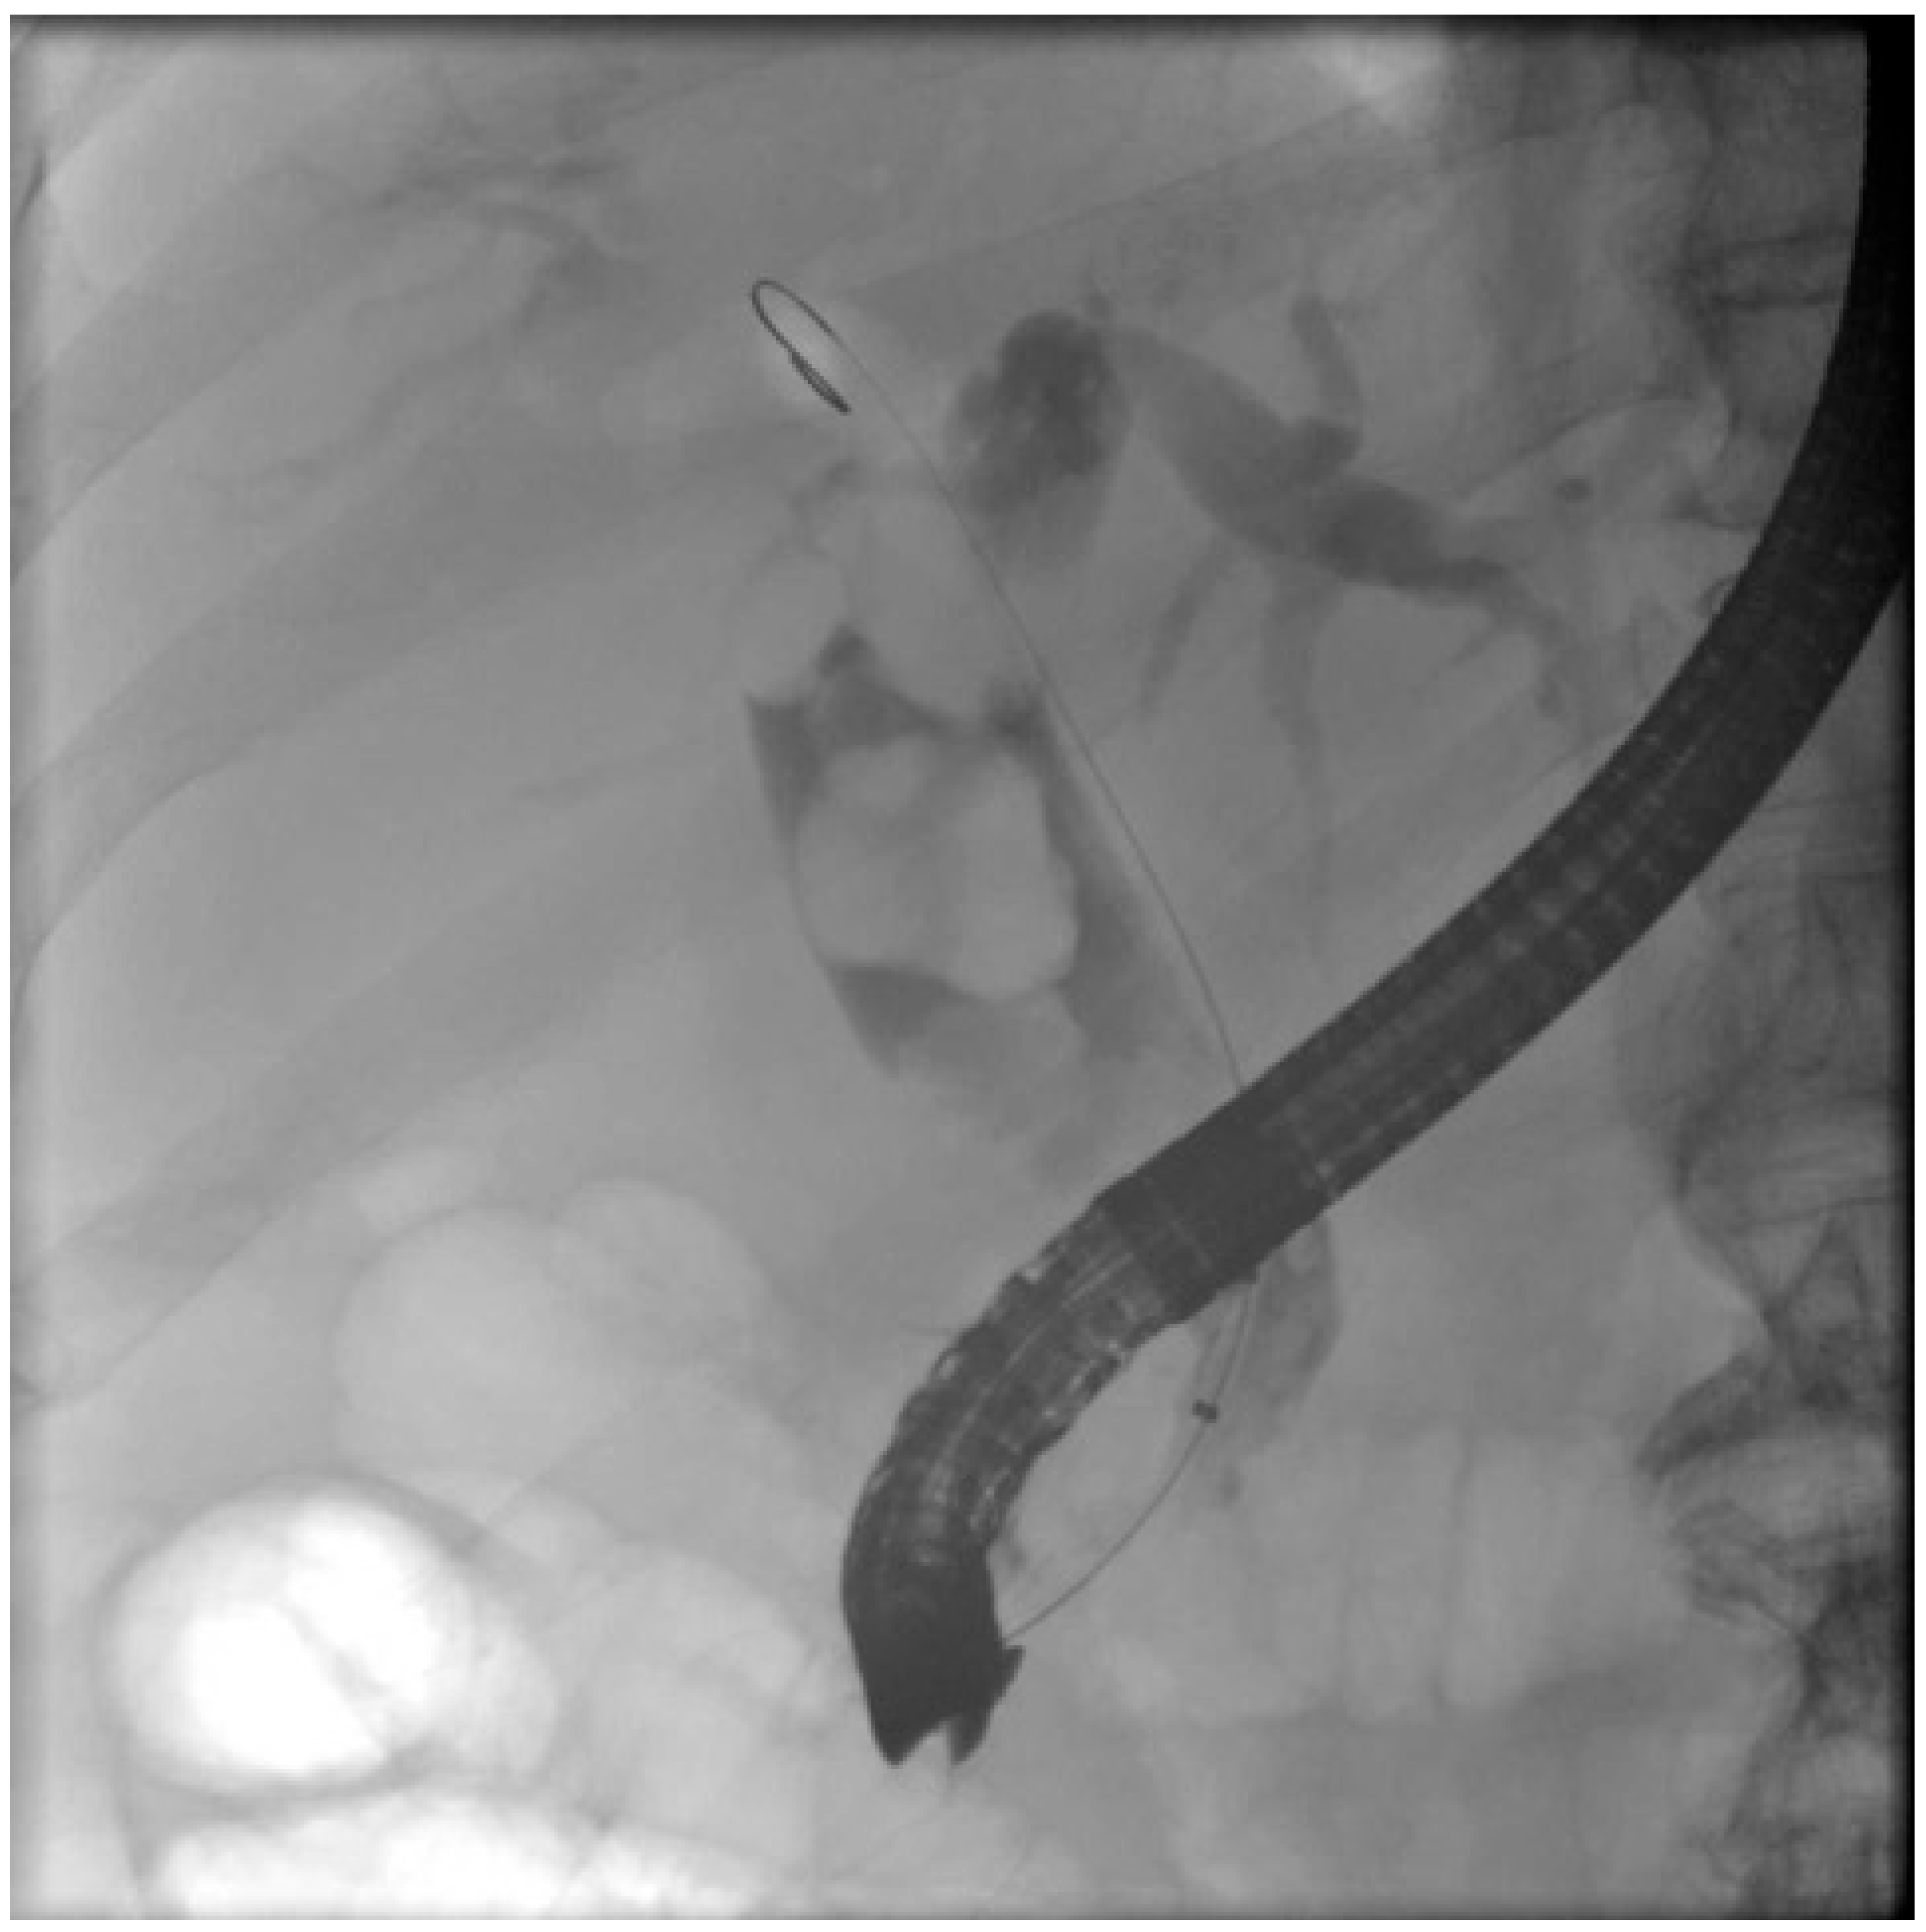

- Kedia, P.; Sharaiha, R.Z.; Kumta, N.A.; Kahaleh, M. Internal EUS-Directed Transgastric ERCP (EDGE): Game Over. Gastroenterology 2014, 147, 566–568. [Google Scholar] [CrossRef]

- James, T.W.; Baron, T.H. Endoscopic Ultrasound-Directed Transgastric ERCP (EDGE): A Single-Center US Experience with Follow-up Data on Fistula Closure. Obes. Surg. 2019, 29, 451–456. [Google Scholar] [CrossRef]

- Dhindsa, B.S.; Dhaliwal, A.; Mohan, B.P.; Mashiana, H.S.; Girotra, M.; Singh, S.; Ohning, G.; Bhat, I.; Adler, D.G. EDGE in Roux-en-Y gastric bypass: How does it compare to laparoscopy-assisted and balloon enteroscopy ERCP: A systematic review and meta-analysis. Endosc. Int. Open 2020, 8, E163–E171. [Google Scholar] [CrossRef] [PubMed]

- Sato, T.; Nakai, Y.; Kogure, H.; Mitsuyama, T.; Shimatani, M.; Uemura, S.; Iwashita, T.; Tanisaka, Y.; Ryozawa, S.; Tsuchiya, T.; et al. ERCP using balloon-assisted endoscopes versus EUS-guided treatment for common bile duct stones in Roux-en-Y gastrectomy. Gastrointest. Endosc. 2024, 99, 193–203.e5. [Google Scholar] [CrossRef] [PubMed]